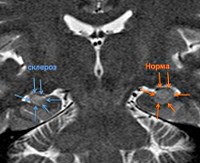

Часто МРТ гиппокампа проводится при наличии судорог (эпилепсии) различного происхождения. Исследователи определили взаимосвязь между частотой приступов, их тяжестью и степенью изменения в этой области мозга. В некоторых случаях наличие мест склероза, обнаруженных с помощью МРТ гиппокампа, подтверждает диагноз эпилепсии и позволяет скорректировать противосудорожное лечение. В последние годы это исследование использовалось для ранней диагностики болезни Альцгеймера, потому что изменение размера гиппокампа является первым проявлением этого заболевания. Благодаря этому после МРТ гиппокампа может быть назначено профилактическое лечение, что задерживает развитие более серьезных расстройств.

При эпилепсии и эпилептическом статусе в структуре этого органа при МРТ гиппокампа выявляются участки склероза. В то же время существует закономерность - чем больше поврежден гиппокамп, тем чаще и тяжелее возникают припадки. В отличие от этого исследования могут быть обнаружены опухоли (как происходящие из мозговой ткани, так и являющиеся метастазами из других очагов). МРТ гиппокампа с синдромом Корсакова или нарушением памяти подтверждает кровоизлияние, дистрофию, опухоли или другие повреждения этой структуры мозга.